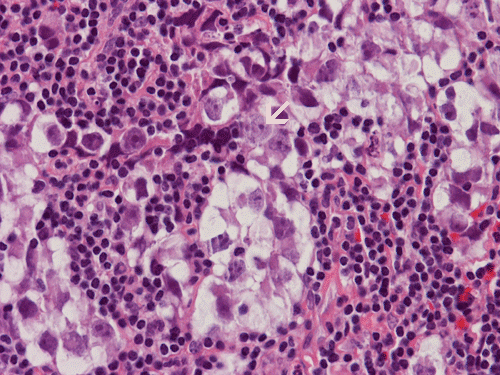

Hematoxylin & eosin

Area  2: The large germinoma cells and the small reactive lymphocytes are in sharp contrast. Pay attention to the large nucleoli (arrow).

• The tumor is composed of large, polygonal cells with prominent nucleoli. These tumor cells also have only a small amount of cytoplasm. The bulk of the cell is occupied by the nucleus. Although enlarged, the tumor cells are rather homogenous in size (Area 2).

• The tumor cells are surrounded by numerous lymphocytes. These are reactive lymphocytes and are mostly composed of T-cells.

The nuclear details of both the germinoma cells and reactive lymphocytes are well demonstrated in this high-magnification photo. Note the large and prominent nucleoli (arrow).